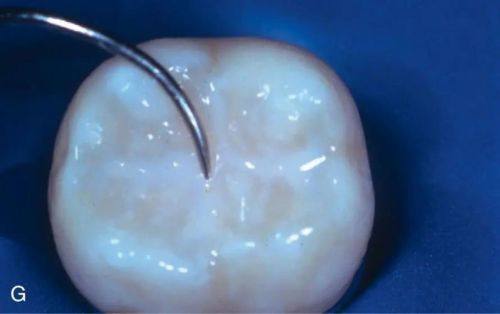

11. 儿童窝沟封闭:100 - 400元